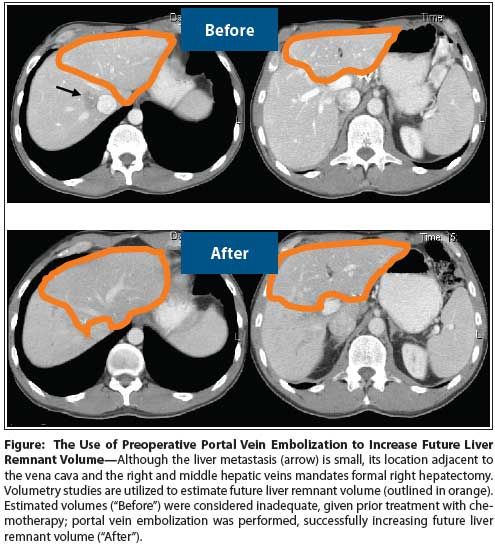

Figure: The Use of Preoperative Portal Vein Embolization to Increase Future Liver Remnant Volume

Preoperative disease workup for synchronous resection includes high-quality CT scans of the chest, abdomen, and pelvis, with triphasic examination of the liver. In patients with hepatic steatosis resulting from chemotherapy or other causes, liver MRI is often used, since it provides better visualization of the parenchyma. Positron emission tomography (PET) scans are not routinely obtained. Liver volumetry (calculation of the future liver remnant volume) is performed for patients being considered for extended hepatic resection; preoperative portal vein embolization can then be performed in patients with inadequate or borderline future liver remnant volumes (Figure).